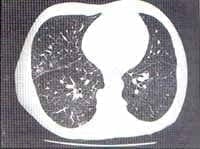

La TAC de tórax pero especialmente la TAC de alta resolución (TACAR), es más sensible que la radiografía del tórax en el diagnóstico de la neumonitis de hipersensibilidad. Los hallazgos dependen del estado de la enfermedad, en la forma aguda se observa consolidación del espacio aéreo y opacidades nodulares pequeñas, mal definidas de 1 a 3 mm de diámetro.

La forma subaguda muestra opacidades en vidrio esmerilado en parches o difusas, nódulos centrolobulillares pequeños, mosaico de perfusión, áreas lobares de atrapamiento de aire a la espiración y fibrosis pulmonar.

En la forma crónica se encuentran hallazgos de fibrosis (dados por engrosamiento intersticial intralobular, engrosamiento de los septos interlobulillar de manera irregular, panal de abeja, bronquiectasias de tracción o bronquiolectasias), opacidades en vidrio esmerilado superpuestas o nódulos centrilobulillares. (29,30,31) figuras No. 7, 8, 9.

Figura 7. Áreas de aumento de la densidad del parénquima pulmonar, que permiten definir los vasos pulmonares conformando un patrón en «Vidrio esmerilado»

Figura 8. Áreas de patrón en «Vidrio esmerilado» y cambios enfisematosos

Figura 9. Presencia de opacidades nodulares centrilobulares pequeñas y engrosamiento septal (con líneas septales)